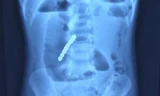

Kết quả siêu âm tim cho thấy, bệnh nhân bị tràn dịch màng tim lượng nhiều. Sau khi hội chẩn khẩn, các bác sĩ đã chuyển bệnh nhân vào khoa Phẫu thuật Tim thực hiện cuộc mổ khẩn nguy. Khi mở lồng ngực bộc lộ tim, ê kíp bác sĩ ghi nhận màng ngoài tim rất căng, không đập, chứa đầy máu.

Mở màng ngoài tim để giải phóng chèn ép, gần 1 lít máu đã trào ra ngập cả khoang trung thất. Qua thám sát, bác sĩ phát hiện một vùng tím, mềm nhũn, ở thành sau thất trái, lan xuống phía mõm tim, diện tích khoảng 6cm2. Thành tim tại vị trí này bị vỡ gây lỗ thủng dài khoảng 7mm.